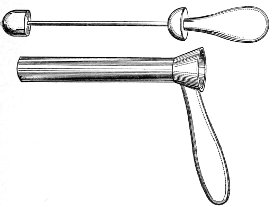

The Vaginal Speculum.—The speculum is an instrument through which a visual examination is made of the vagina, the external os uteri, and the vaginal cervix. A 29 great number of specula have been invented. At the present day the best two instruments of this class are the bivalve speculum, such as Goodell’s (Fig. 6), and the duck-bill speculum (Fig. 7), or perineal retractor, invented by Sims.

Fig. 6.—Goodell’s speculum.

The bivalve speculum is introduced with the woman upon her back, in the dorso-sacral position already described. The vulva and the vagina should be cleaned. The speculum should be warmed by placing it in hot water, and should then be lubricated with the soap solution or with vaseline. It should be introduced with the blades closed and the plane of the blades lying not exactly 30 in the median sagittal plane of the body, but inclined at a small acute angle to this plane, one edge of the speculum being directed toward either vaginal sulcus. The instrument is passed into the vagina toward the position in which, by a previous digital examination, the vaginal cervix had been found to lie. The instrument is then turned with the handles toward either thigh, so that the blades become parallel to the anterior and posterior vaginal walls, in order that, when separated, they will open the vaginal slit. The handles are brought together and the blades opened. When the vaginal cervix comes well into view the blades are fixed in place by the screws (Fig. 9).

Fig. 9.—Goodell’s speculum in position.

In some cases, where the cervix points well forward or well backward, it may be readily brought into view through the speculum by catching it with a tenaculum.

By means of the bivalve speculum we are able to make a partial inspection of the vaginal walls, an imperfect inspection of the vaginal vault, and a good inspection of the vaginal cervix and the external os. Applications 31 can be made to the cervix, but none of the minor operations of gynecology can be performed through this speculum.